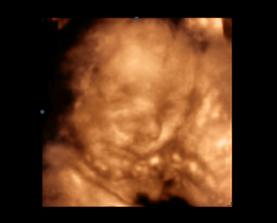

Som v 25tt a mame za sebou 3Dcko, videli ms emaleho braceka a mame DVD aj fotky, maly sa podoba na svojho starsieho brata, minimalne perami 🙂